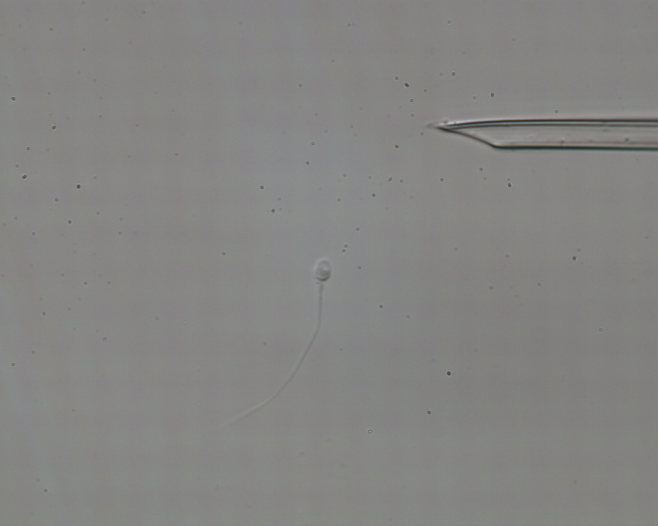

H μέθοδος της ενδοκυτταροπλασματικής έγχυσης (ICSI) παρέχει τη δυνατότητα στον εμβρυολόγο να επιλέξει τα φαινομενικά καλύτερα σπερματοζωάρια, τα οποία με τη χρήση ειδικής πιπέττας τα μεταφέρει στο εσωτερικό των ωαρίων, διαδικασία που αυξάνει κατά πολύ την πιθανότητα γονιμοποίησης.

Η επιτυχία της μεθόδου στηρίζεται στη μεγέθυνση των σπερματοζωαρίων στο μικροσκόπιο κατά 400 έως 600 φορές, ώστε να είναι πιο ευδιάκριτα τα μορφολογικά τους χαρακτηριστικά και ο εμβρυολόγος να μπορεί να επιλέξει μόνο όσα έχουν μεγαλύτερες πιθανότητες να γονιμοποιήσουν επιτυχώς τα ωάρια.

Για την ανίχνευση αυτών των ιδιαίτερων "μικροσκοπικών" χαρακτηριστικών αναπτύχθηκε η τεχνολογία IMSI, η οποία χρησιμοποιεί φακούς στο μικροσκόπιο, που επιτυγχάνουν τη μεγέθυνση των σπερματοζωαρίων έως και 10.000 φορές.

Η μέθοδος IMSI επιτρέπει στον εμβρυολόγο να επιλέξει με μεγαλύτερη ακρίβεια και ασφάλεια, μόνο όσα σπερματοζωάρια εμφανίζουν την ιδανική μορφολογία, και κατά συνέπεια έχουν τις περισσότερες πιθανότητες επιτυχούς γονιμοποίησης, ανάπτυξης βλαστοκύστεων και εγκυμοσύνης.